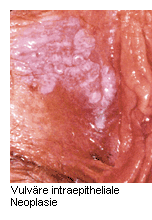

Das klinische Erscheinungsbild der VIN ist sehr heterogen: Flache oder erhabene Erosionen der Haut können weißlich, rötlich oder pigmentiert erscheinen. Auch die Bildung von Ulzera ist möglich. Meist treten Symptome wie Pruritus oder Schmerzen auf, doch vielfach sind die Vulvaläsionen auch symptomlos. Zur Absicherung der Verdachtsdiagnose ist eine Biopsie unter Lokalanästhesie erforderlich.